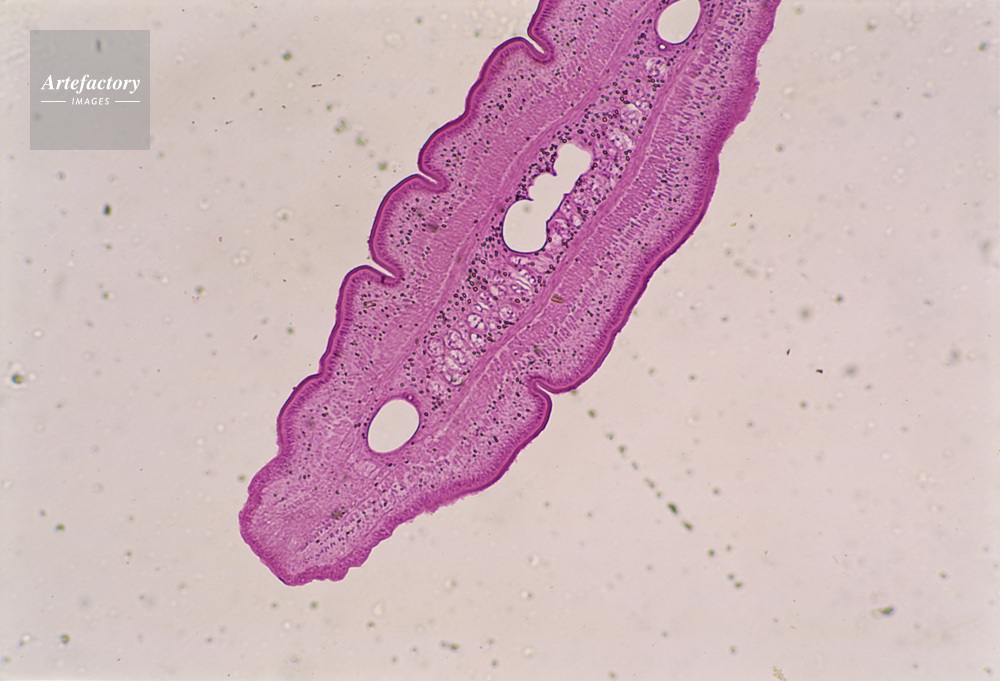

| キャプション | ムコウジョウチュウ,20倍 | 制限事項 | ||